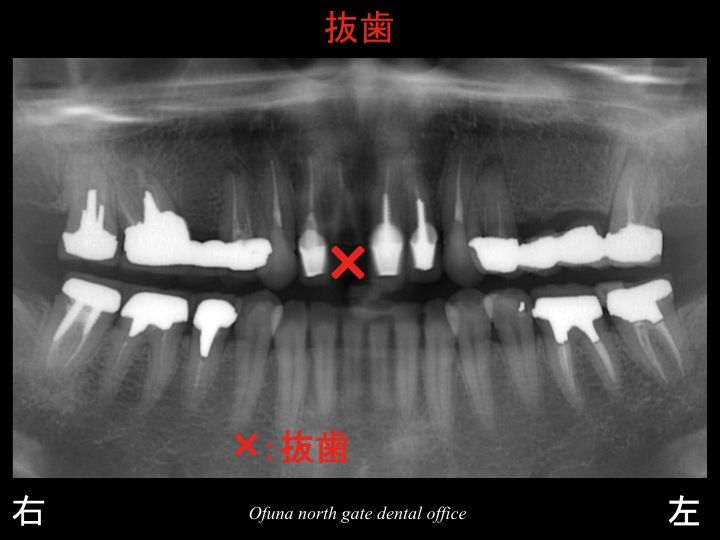

以下が初診時です。

上顎前歯部の被せ物が取れて、他歯科医院で診断してもらったところ

歯根破折 を起こしており、抜歯しか方法がないと言われ、なにか方法はないかと考え、当医院を受診した方です。

当医院でもレントゲン等の診査を行った結果、

最初に受診した歯科医院と同様の診断で、

歯根破折 でした。

この歯根破折 した歯は抜歯になります。

抜歯しか方法がないのです。

ここで この患者様の口腔内全体を見てみましょう!

以下のレントゲン写真の赤丸は神経がない歯です。

ほとんどの歯が神経がありません。

今後が本当に心配な方です。